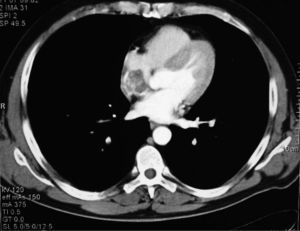

Los tumores primarios cardíacos son una entidad poco común. Su incidencia varía entre el 0,0017 y el 0,033% según las series consultadas1,2. En autopsias sistemáticas se encuentran en el 0,2% de los casos y la mayoría son benignos (90%)1. Entre los tumores cardíacos primitivos malignos destacan, por su frecuencia, los sarcomas (76-78%), y el angiosarcoma es el más frecuente en adultos1–3, que predomina entre la segunda y la quinta década de la vida3 y en el sexo masculino2–4. Dos tercios de los angiosarcomas se localizan en la aurícula derecha aun cuando tienen mejor pronóstico los alojados en la aurícula izquierda. Caso clínico: varón caucásico de 45 años de edad, sin alergias conocidas ni antecedentes personales de interés. Ex fumador de 10 cigarrillos desde hace 2 años. Sin hábitos tóxicos. En su historia familiar destaca el fallecimiento de su padre a los 57 años por neoplasia gástrica, el de su madre a los 65 años por melanoma con enfermedad ósea diseminada, el de su hermano a los 45 años por neoplasia de pulmón, su hermana a los 42 años por metástasis cerebral con neoplasia de pulmón primaria y otra hermana a los 57 años por sarcoma hepático. Encontrándose previamente bien presentó crisis focal (clonía del hemicuerpo izquierdo) con posterior generalización. En la exploración neurológica se objetivó disartria y paresia crural distal izquierda (4/5) con Babinski. La auscultación cardíaca fue rigurosamente normal. En las pruebas complementarias realizadas no se observaron alteraciones significativas en hemograma, bioquímica, inmunidad, coagulación ni gasometría arterial. Las serologías realizadas para descartar lesiones cerebrales de origen infeccioso (VIH, citomegalovirus, toxoplasma) fueron negativas. Se objetivó elevación de la enolasa sérica (33,6ng/ ml) con normalidad de los demás marcadores tumorales. Las pruebas de neuroimagen realizadas (tomografía computarizada [TC] y resonancia magnética [RM] cerebral) (fig. 1) revelaron una imagen compatible con metástasis única parietal derecha con pequeña hemorragia concomitante. Una TC torácica (fig. 2) reveló nódulos pulmonares metastásicos y una tumoración en la aurícula derecha informada en el ecocardiograma como imagen neoformativa de 59 × 42 × 30mm, redondeada, amplia base de implantación, densidad variable, bordes policíclicos con pequeñas zonas móviles en su superficie. El resto del estudio (broncoscopia, gammagrafía ósea, colonoscopia, pruebas funcionales respiratorias) fue normal. La biopsia de un nódulo pulmonar mediante toracoscopia fue compatible con angiosarcoma cardíaco en estadio IV. El paciente fue tratado con radioterapia holocraneal y quimioterapia paliativa con taxol semanal a dosis de 127,5mg, descartándose la cirugía, y falleció a los pocos meses por complicaciones infecciosas secundarias. El angiosarcoma cardíaco, por su baja frecuencia y su dificultad diagnóstico-terapéutica, supone un reto clínico importante. Dadas su agresividad y la frecuencia de metástasis al diagnóstico, las opciones de tratamiento son limitadas2. La mayoría de las veces es asintomático hasta fases avanzadas del proceso5. La clínica de presentación es muy variada, bien por crecimiento local del tumor (alteración del flujo cardíaco o de la función valvular) que va afectando al pericardio y estructuras vecinas (pericarditis, taponamiento cardíaco, arritmias, embolia tumoral) o bien por su extensión a distancia2–5. Las metástasis son frecuentes al diagnóstico de la enfermedad y los pulmones, hígado y cerebro son las localizaciones más habituales2, hecho que empeora de forma clara el pronóstico1,4,5. La supervivencia de los pacientes oscila en 9–12 meses tras el diagnóstico si no se puede resecar el tumor1,3. En general, el desarrollo de las pruebas de imagen (TC helicoidal y RM) ha mejorado el diagnóstico antes de la cirugía1,5. El tratamiento indicado de forma generalizada en pacientes sin enfermedad a distancia es la cirugía resectiva radical en combinación con quimioterapia y/o radioterapia adyuvante1,2. Algunos autores proponen el trasplante cardíaco como alternativa quirúrgica; sin embargo, las supervivencias obtenidas no difieren de las conseguidas con cirugía convencional1,2,5.